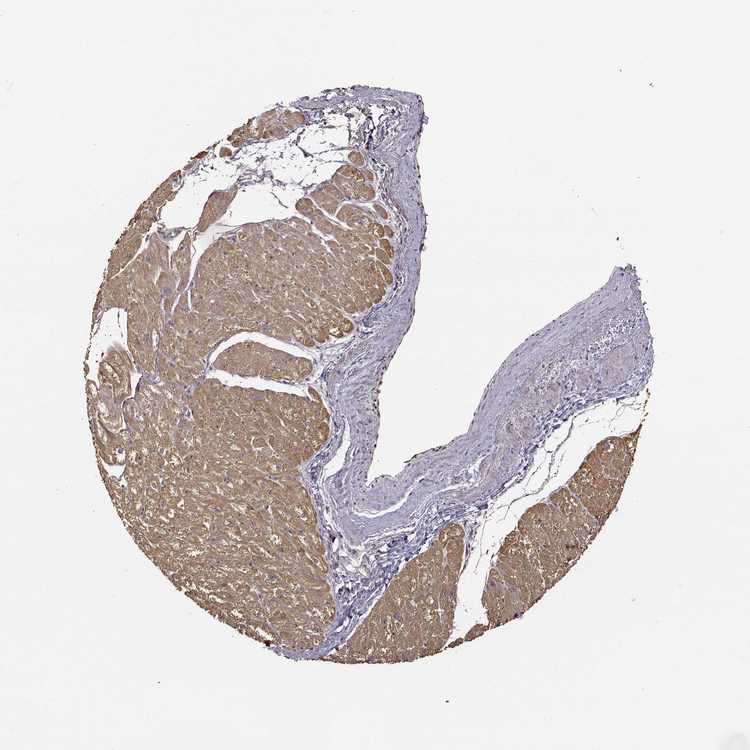

HEART MUSCLE - Antibody stainingi

Antibody staining in the annotated cell types in the current human tissue is reported as not detected, low, medium, or high, based on conventional immunohistochemistry profiling in selected tissues. This score is based on the combination of the staining intensity and fraction of stained cells.

Each image is clickable and will lead to virtual microscopy that enables deeper exploration of all samples and also displays staining intensity scores, fraction scores and subcellular localization as well as patient and tissue information for each sample.

Antibody HPA000556

Cardiomyocytes Medium